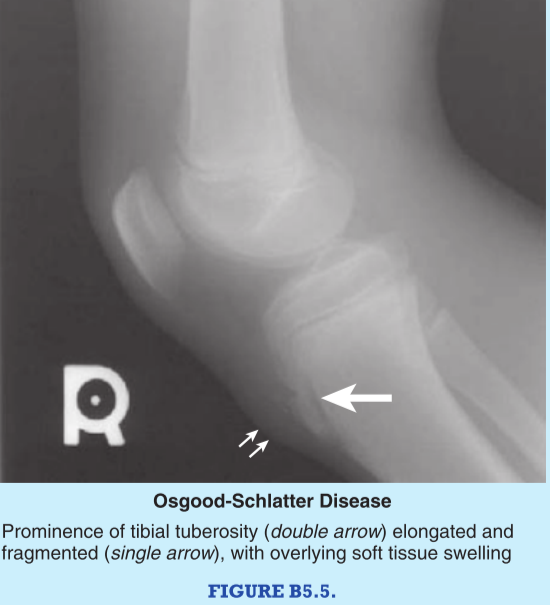

What causes Osgood-Schlatter disease and what are its symptoms?

Osgood-Shlatter disease is inflammation of the tibial tuberosity and chronic recurring pain caused by disruption of the epiphyseal plat at the tibial tuberosity.